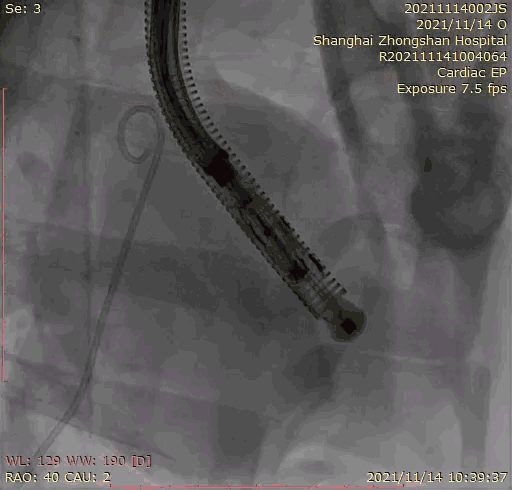

本次臨床前研究經(jīng)右側(cè)頸靜脈置入LuX-Valve Plus輸送系統(tǒng)可調(diào)彎鞘管,在DSA及超聲引導(dǎo)下將人工三尖瓣瓣膜植入到原有三尖瓣位置,利用獨(dú)特的錨定技術(shù)將人工瓣膜支架可靠固定在預(yù)定的位置。

上海中山醫(yī)院葛均波院士、錢菊英院長(zhǎng)、周達(dá)新教授、潘文志教授、潘翠珍教授、李偉教授共同完成此次臨床前研究。術(shù)后葛均波院士對(duì)Lux-Valve Plus的器械操作性能給予了高度評(píng)價(jià),DSA和超聲影像也顯示出在本次研究中Lux-Valve Plus的安全性和有效性俱佳。